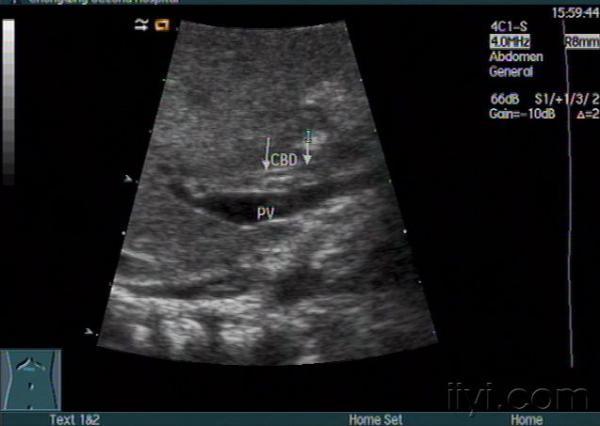

胆道闭锁?

小儿黄疸,是胆道闭锁吗??

图像没有胆道闭锁的征象啊!越来越不易啊